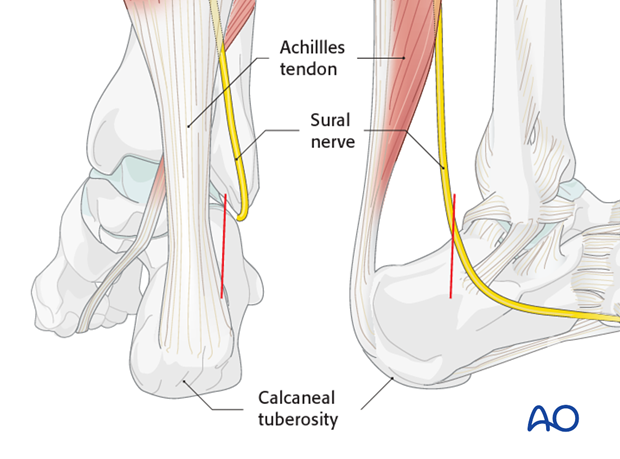

MIO posterior approach to the calcaneus

Posterior Heel Spur Diagnosed Treated by Foot Surgeons Mercy in Baltimore

Bone spurs of the heel of foot defined and treatments